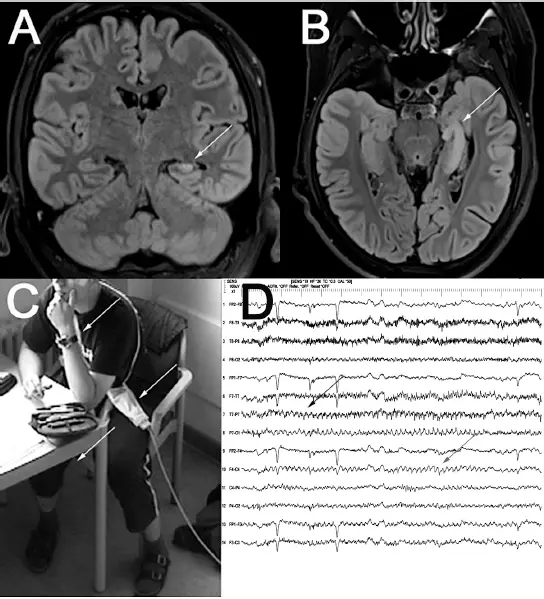

Ein erstes nicht-invasives Video-EEG-Monitoring mit 41 nach dem 10-10-System geklebten Hautelektroden ergab ein unauffälliges EEG ohne epilepsietypische Potenziale, ohne EEG-Änderung bei zehn habituellen Angstzuständen. Es folgte vier Monate später ein erneutes Monitoring in der Hoffnung, doch noch einen intensiveren, eventuell mit Aphasie einhergehenden Zustand aufzuzeichnen, wiederum mit normalem interiktualem EEG. Unter den mehr als elf Angstzuständen ergab sich lediglich einmal im EEG der schließlich doch nicht tragfähige Eindruck eines Anfallsmusters links temporal; beim Betrachten des Videos entlarvte sich das Theta-Muster als Artefakt durch Wippbewegungen des rechten Beins, mit Kontakt des Körpers zum Kabelbaum. Das Artefakt zeigte in typischer Weise ein unlogisches Feld links- und rechtshemisphärisch (Schulz 2011). Das MRT ergab eine Hippokampussklerose links (  Abb. 2.1).

Abb. 2.1).

Abb. 2.1: (A, B) MRT, koronare und axiale Schnittführung, FLAIR-Sequenz: Hippokampussklerose links, durch Pfeile markiert (nebenbefundlich und epileptologisch irrelevant: Arachnoidalzyste rechts temporal anterior). (C) Patient macht schnelle wippende Bewegungen mit dem rechten Bein; der Kabelbaum liegt über den Beinen (mit Pfeilen markiert). (D) EEG-Ableitung, temporale Längsreihen, rechts über links: Artefakt: rhythmisches Thetamusters links temporal (schwarzer Pfeil), aber auch rechts frontozentral (grauer Pfeil: Kanal C4-P4). Kein EEG-Anfallsmuster.